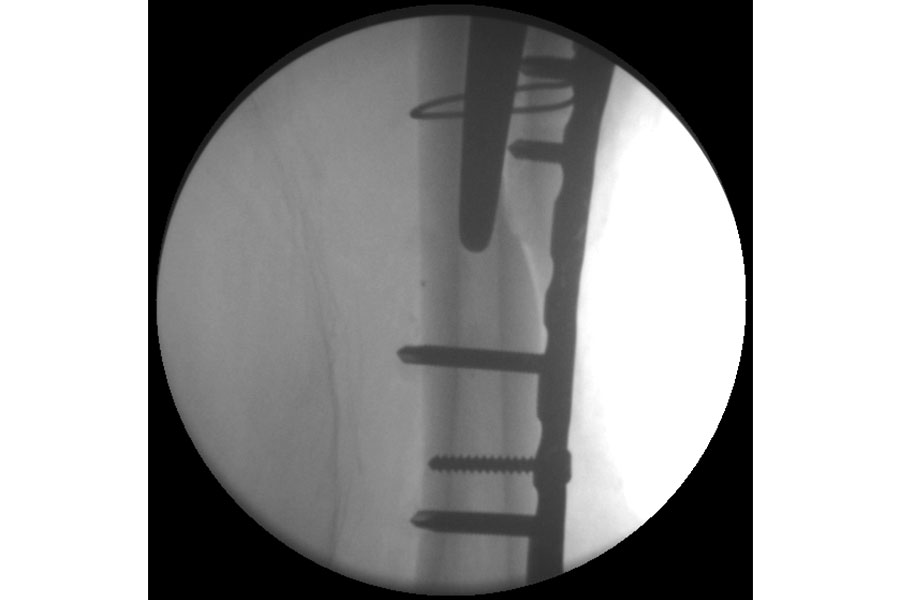

Trauma

Case 1